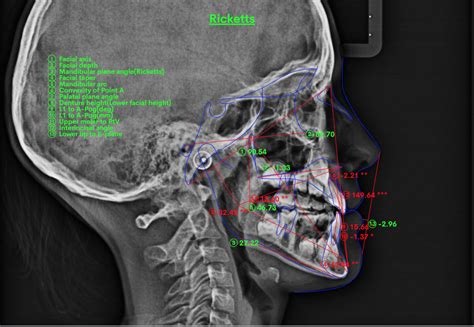

La ortodoncia se encuentra en la era del análisis facial, donde la evaluación cefalométrica juega un papel crucial en la planificación del tratamiento y el pronóstico. Un buen análisis cefalométrico permite clasificar las maloclusiones de mordida abierta y es esencial para la identificación de la etiología de dicha maloclusión, facilitando así el tratamiento adecuado y estable.

Tipos de Análisis Cefalométricos

Existen diversos métodos para realizar un análisis cefalométrico completo. A continuación, se describen algunos de los más utilizados:

El ángulo FMA, formado por el plano mandibular y el plano horizontal de Frankfurt, muestra el patrón de crecimiento facial. Es importante interpretar sus resultados para determinar si el patrón se desvía del normal.

Diseñado por el Dr. Young H. Kim, el ODI es la suma aritmética del ángulo del plano A-B al plano mandibular, y el ángulo del plano palatino al plano horizontal de Frankfort. Un valor de 68º o menor indica una mordida abierta esquelética o tendencia a ella.